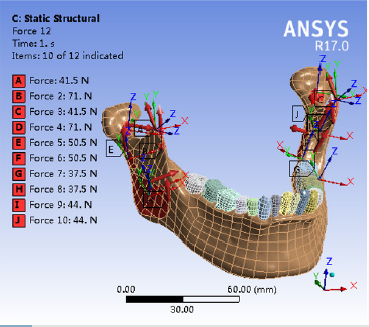

It was assumed that the mandible, teeth, fibula and other tissues are isotropic, homogeneous and continuous elastic materials. With reference to some published research data [17-19], the modulus of elasticity and Poisson’s ratio were set. The mandibular condyles on both sides were fixed and restrained to prevent the mandible from moving, and the characteristics of the stress distribution of the mandible were analyzed. The chin was also fixed and the changes in the displacement of the mandible and condyle were analyzed. Vertical combined loading was applied on the healthy side posterior area by applying 200 N and 175 N to the mandibular first and second molar areas, respectively [20]. The medial pterygoid was loaded with 44 N, the deep and superficial layers of the masseter were loaded with 50.5 N and 37.5 N, respectively; the posterior and anterior portions of the temporalis were loaded with 41.5 N and 71 N, respectively, and the lateral pterygoid muscle was loaded with 5.5 N (Figure 2) [21,22].